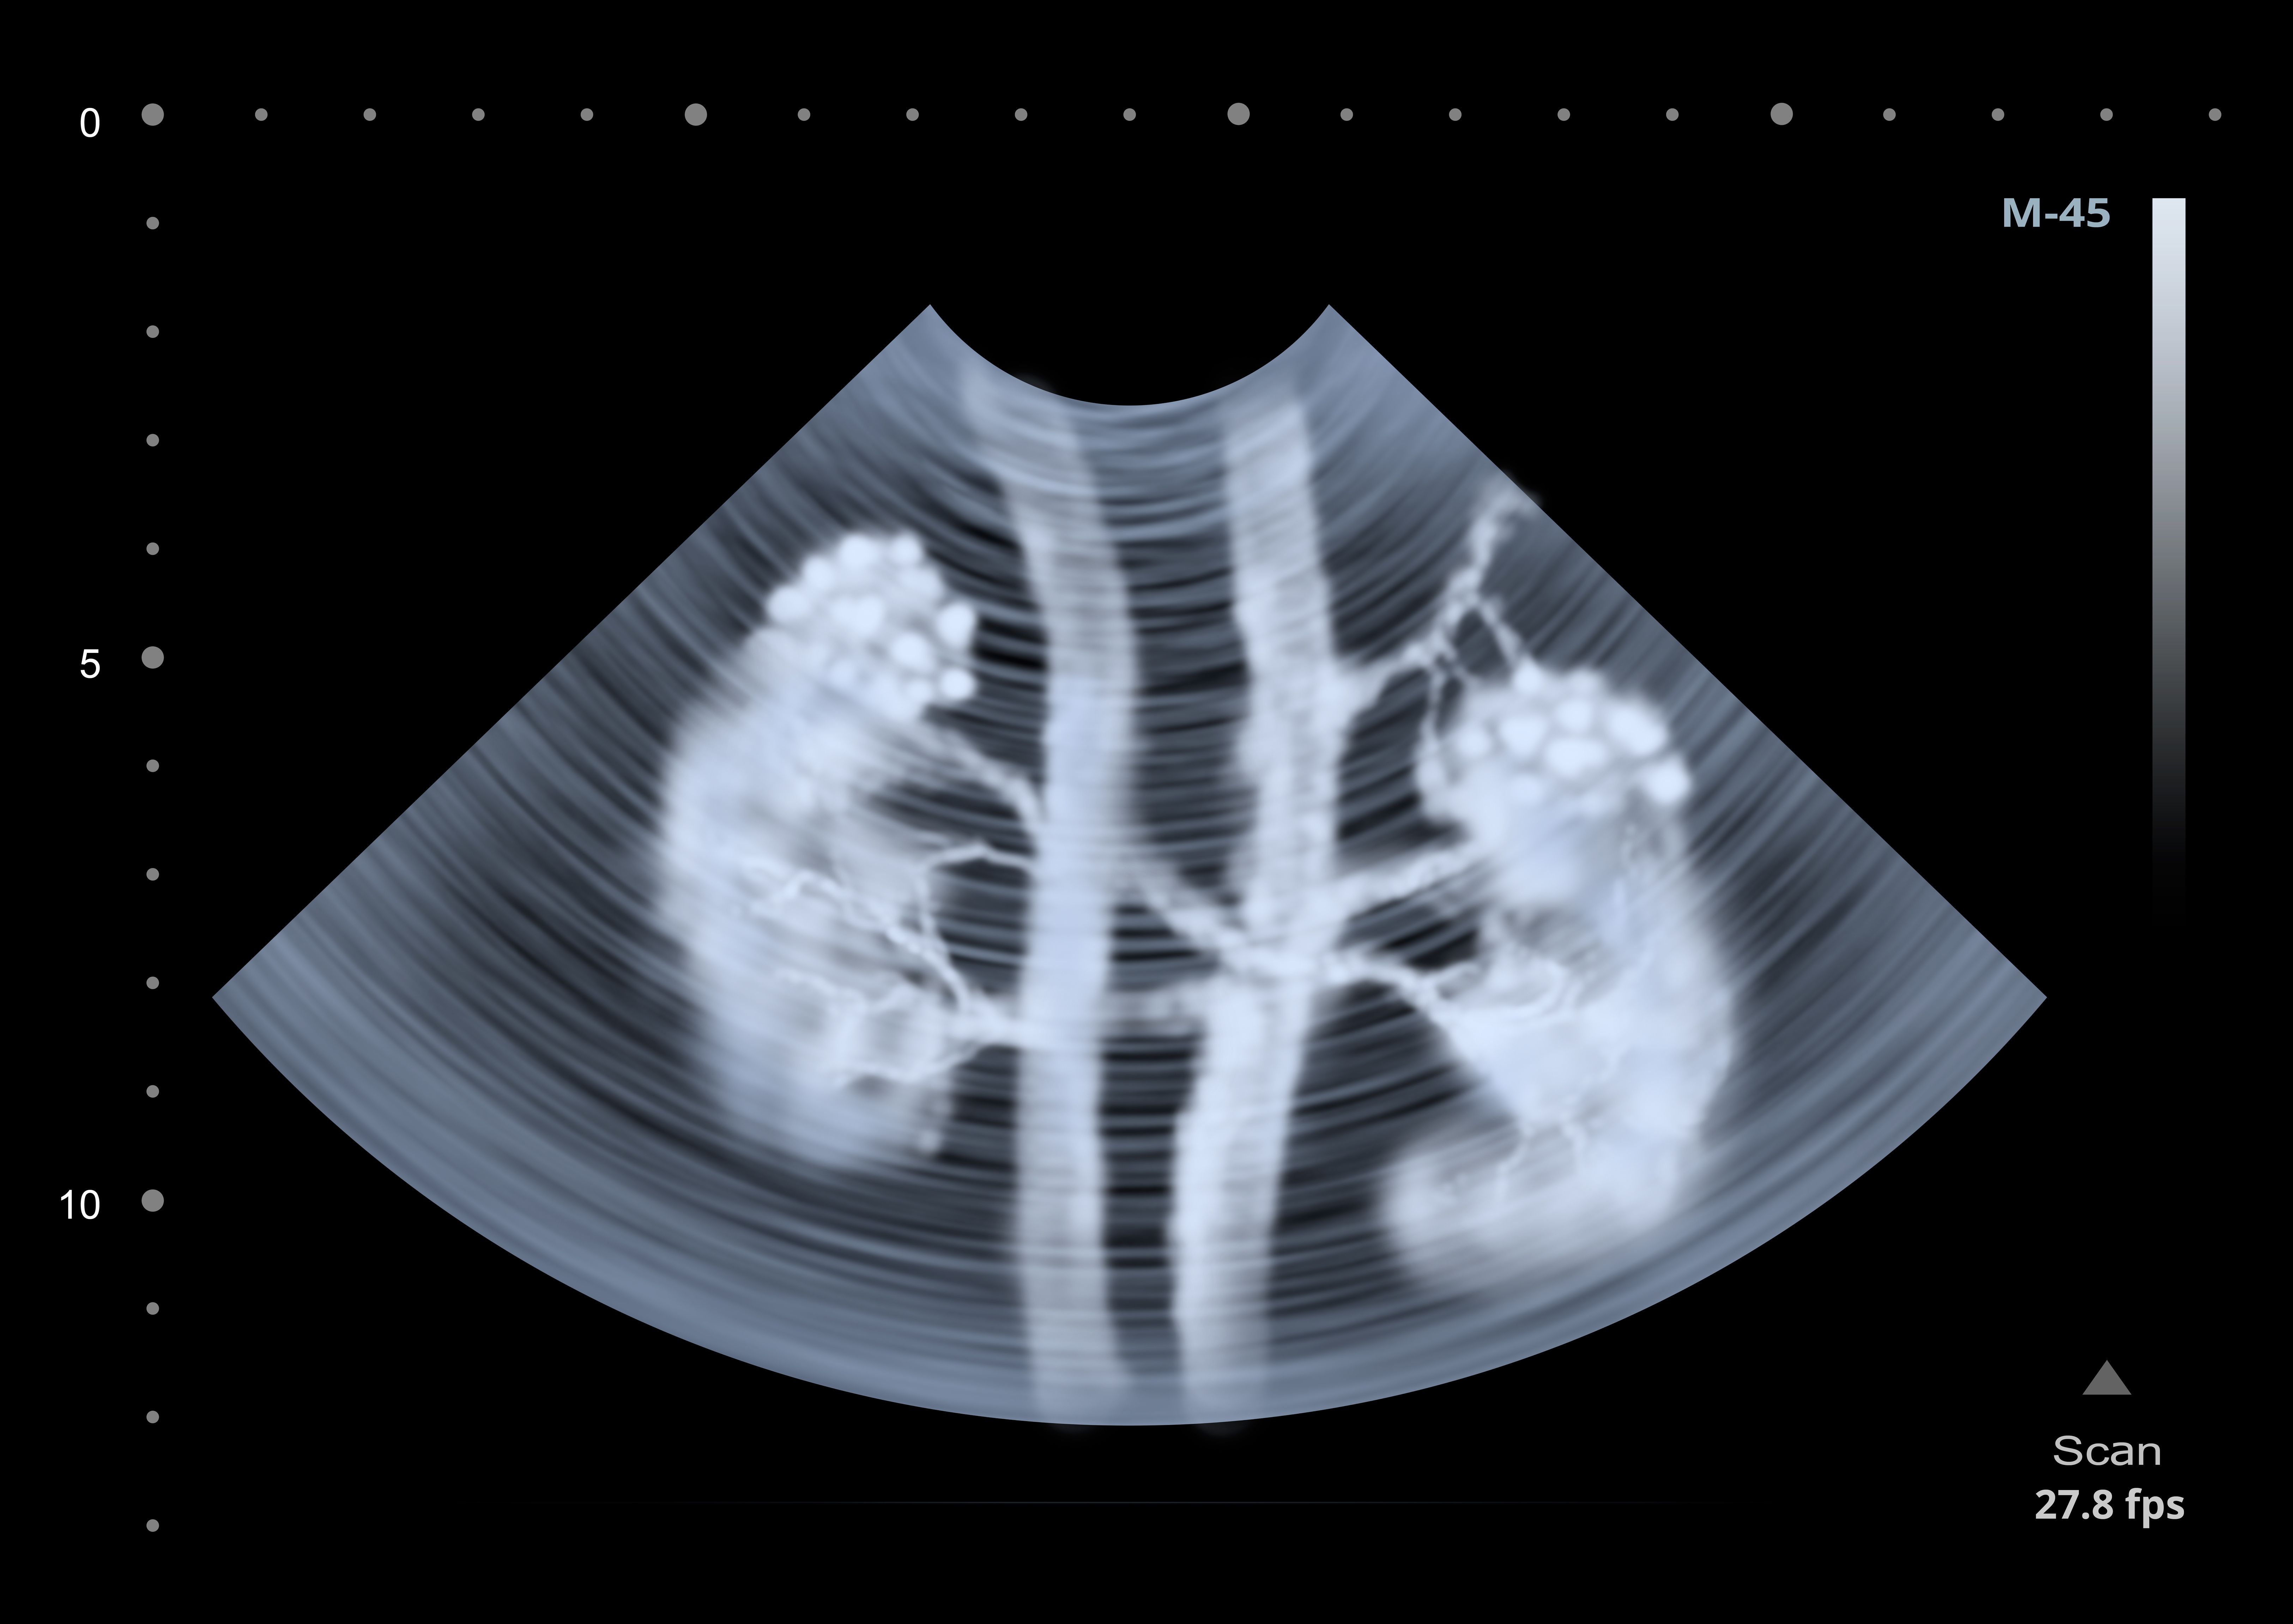

The first step in reducing the burden of infection during lupus nephritis is understanding where and how it happens.

In lupus patients, urinary CD4 T cell counts correlate selectively and specifically with disease activity and renal involvement, well enough to be used to monitor the progress of treatment.